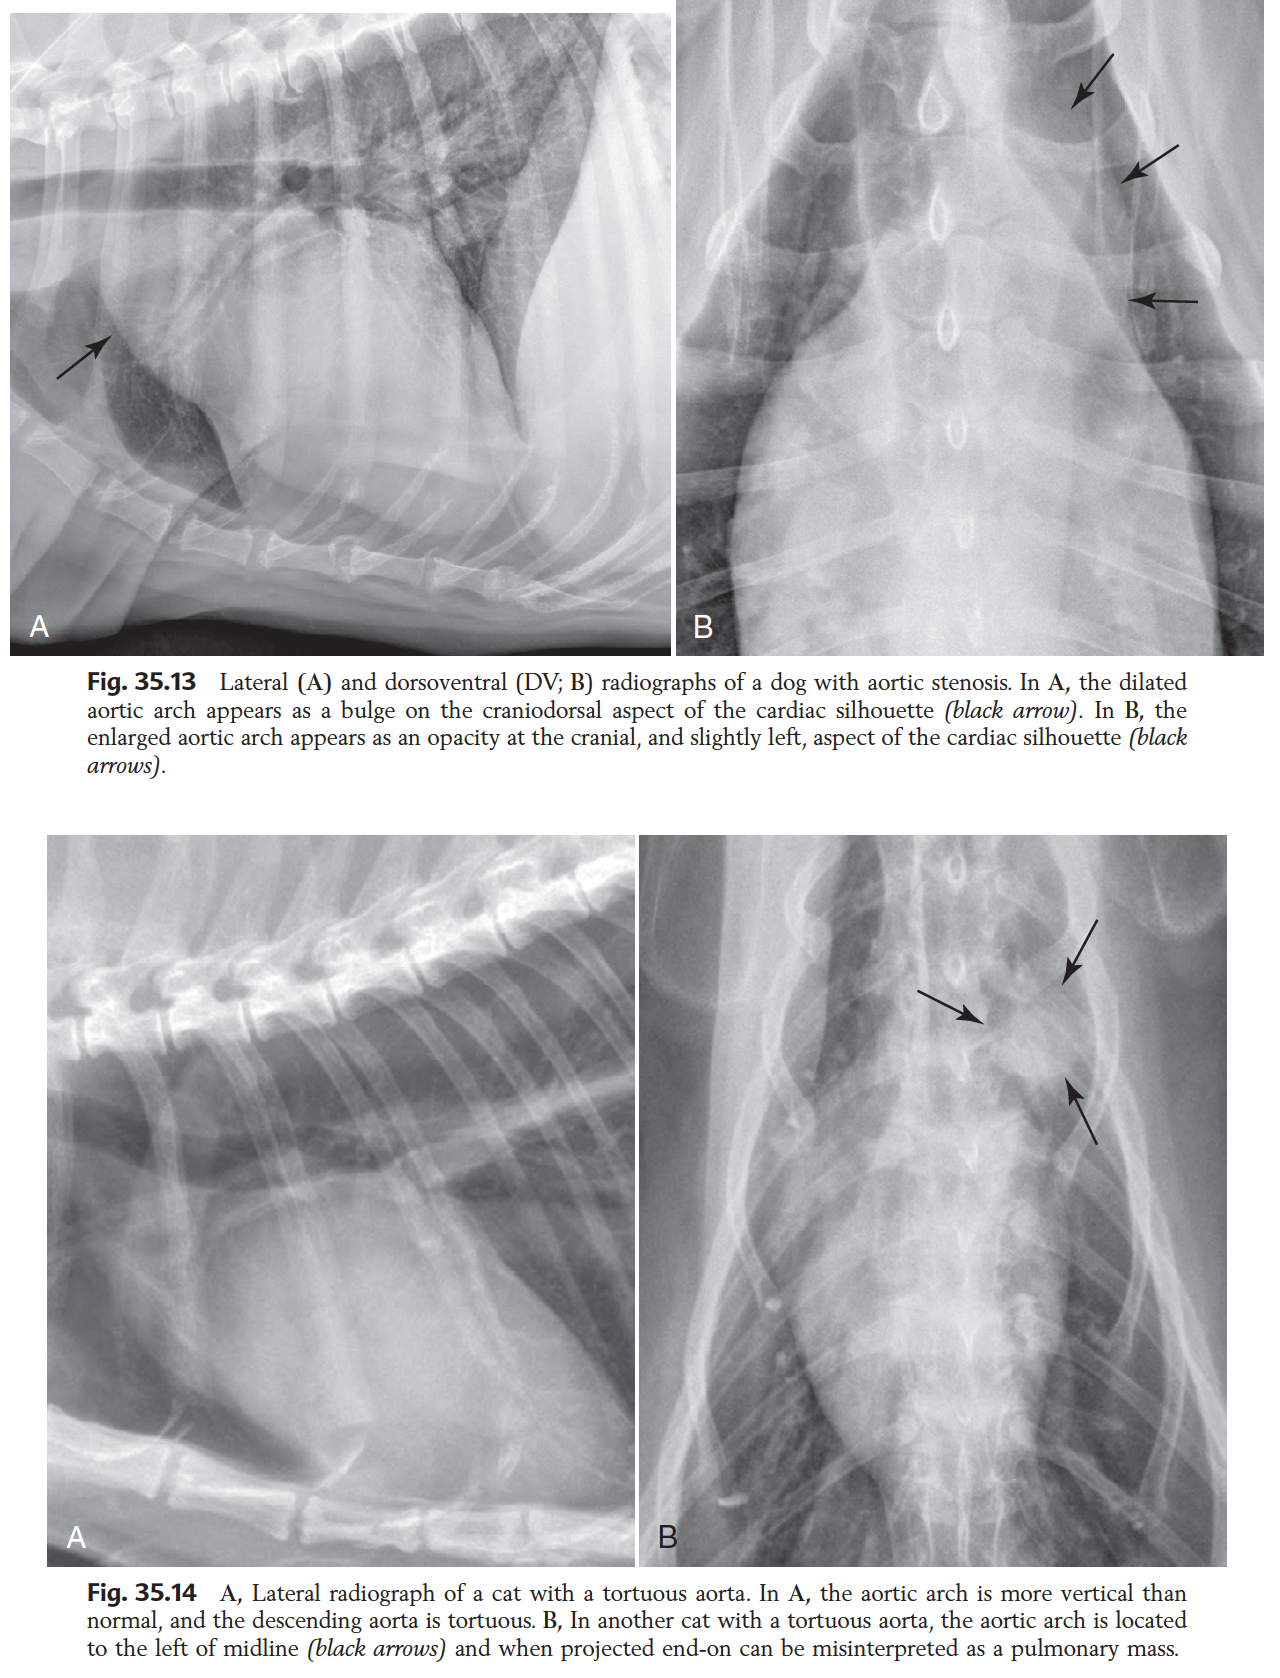

Rx features of Ao enlargement

Lat:

- Inc. mass at craniodorsal aspect

VD/DV: